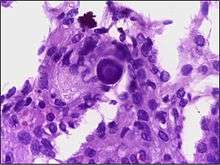

Micrograph of psammoma body in the centre of the field in a meningioma of brain. H&E stain.

A psammoma body is a round collection of calcium, seen microscopically. The term is derived from the Greek word ψάμμος (psámmos), meaning "sand".

Psammoma bodies usually have a laminar appearance, are circular, acellular and basophilic.